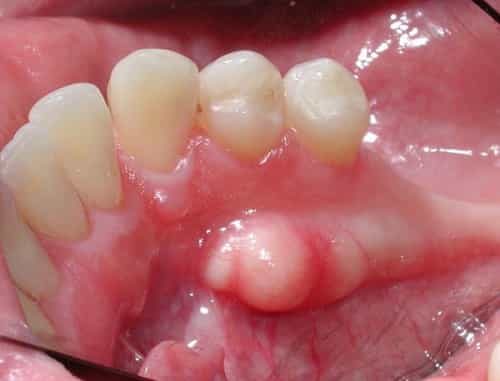

¿Qué es Torus (Tori)?

TORUS (TORI) Los toros son básicamente depósitos óseos adicionales que se han formado en los huesos maxilares superior o inferior. Cuando el hueso adicional se encuentra en el paladar duro, se denomina torus palatinus. Si los toros se encuentran en la mandíbula inferior, se consideran toros mandibulares (ya que la mandíbula inferior se conoce como mandíbula). La buena noticia es que la mayoría de los toros son en realidad benignos (no cancerosos) y no necesitan ningún tratamiento.